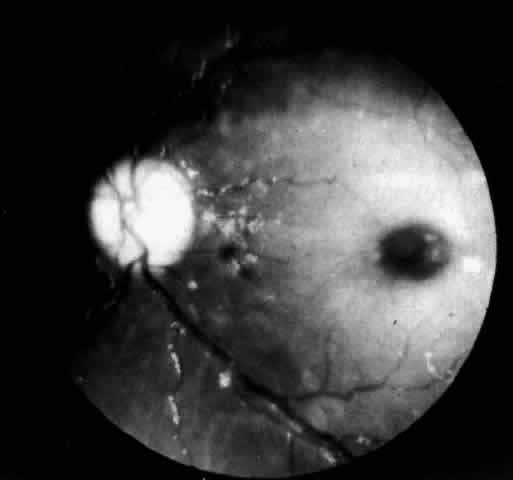

Hex, hexosaminidase. A more widespread opacification of the retina can occur due to involvement of the ganglion cells in the posterior pole. This was observed by Wray4 in a 3½-year-old child with Tay-Sachs disease. The child had black hair and brown eyes, and the cherry-red spot at the macula was brown. The patient was blind, with marked optic atrophy (Fig. 4).